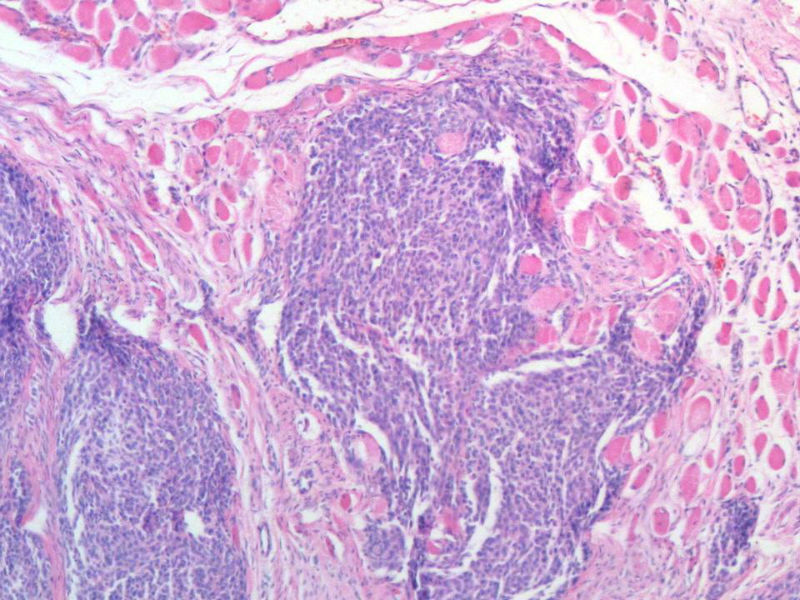

女,64岁,头晕半月,CT检查颅内左颞叶占位,侵犯颅骨和颞肌,手术切除肿物。肉眼,灰白色结节状肿物,3X3X2厘米,边界不清,切面灰黄色,质软。

特别提示:手术前曾做过介入肿瘤栓塞。镜下核分裂15/HP。脑左颞部占位图1

恶性脑膜瘤,有肌肉和骨的侵犯。

梭形细胞与上皮样漩涡状结构,富于细胞,见个别沙砾体,并见肿瘤性坏死。颅骨及其横纹肌等软组织内见肿瘤呈侵袭性生长。但细胞异型性不是很大。鉴别:

1)恶性脑膜瘤

2)非典型性脑膜瘤

由于非典型性脑膜瘤也可以发生地图状坏死,甚至侵袭性生长。需要计数核分裂数/10HPF,以资鉴别诊断。